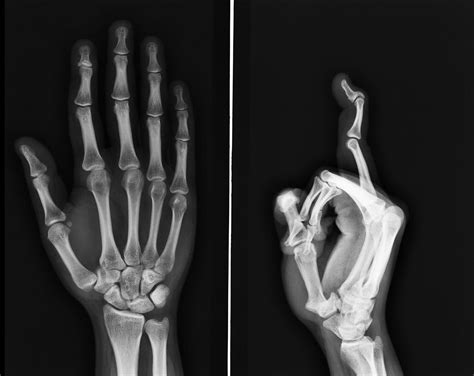

Have you ever noticed someone bending their fingers back at an impossible angle, or perhaps you are the one capable of performing such party tricks? Often referred to colloquially as having Double Jointed Finger Bones, this phenomenon is a fascinating aspect of human anatomy that draws both curiosity and concern. While the term itself suggests a structural multiplication of bone segments, the reality is far more nuanced, rooted in the science of joint hypermobility. Understanding why some individuals possess a greater range of motion in their fingers requires a closer look at the connective tissues, genetics, and the physiological structures that hold our skeletal system together.

Contrary to the popular myth, having Double Jointed Finger Bones does not mean you have extra bones or joints. Instead, the condition is medically classified as joint hypermobility. This means that your joints have a range of motion that exceeds the average for a healthy individual of your age and sex. The primary culprits behind this flexibility are the components of the joint capsule and the surrounding ligaments and tendons.

In most people, ligaments act like sturdy rubber bands that hold bones together while restricting movement to a safe range. In individuals with hypermobility, these tissues—primarily composed of collagen—are more elastic or lax. This inherent "looseness" allows the fingers to hyperextend or bend beyond the typical limits. It is a biological variation that often runs in families, suggesting a strong genetic component influencing the structure of connective tissues throughout the entire body.